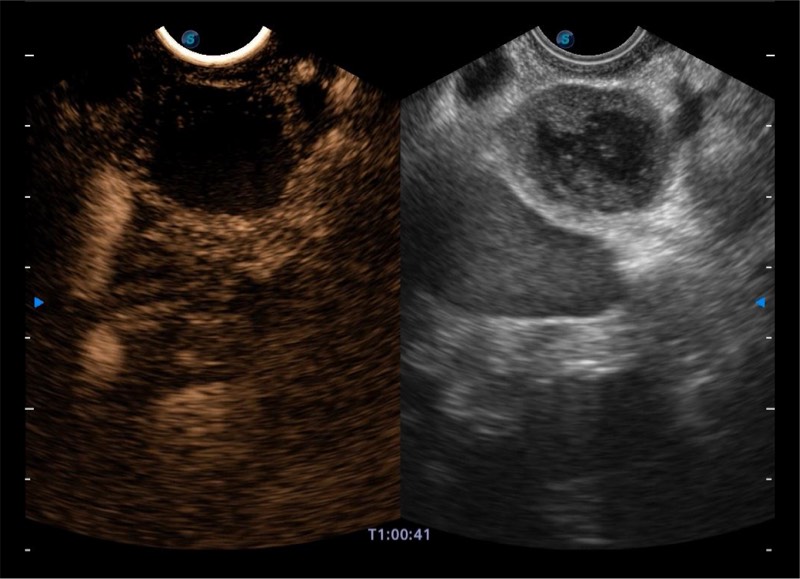

基于二十年的超声技术积累,银河优越会提供了最新一代的独立超声主机,在提供高质量图像的同时满足多学科使用。具备常见多普勒技术并提供弹性成像、声学造影等高端影像技术。新一代传感器具有更强的抗干扰能力并减少图像伪影。

4-12MHZ宽频输出